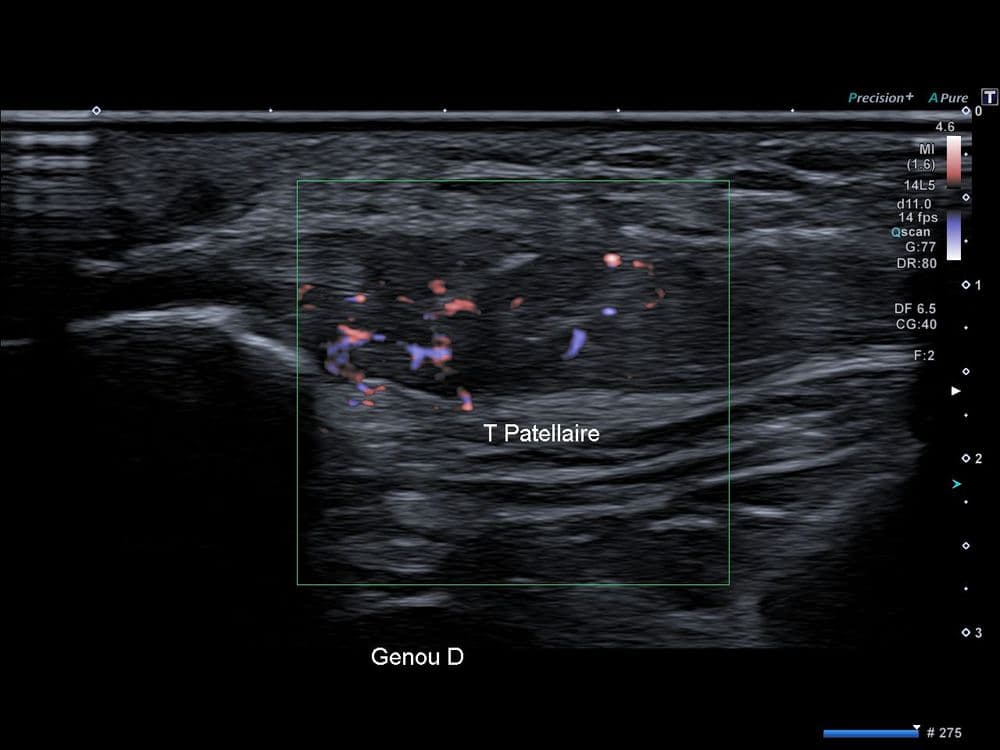

Gonalgie antérieure persistante à type de crise intermittente non prévisible ainsi que lors du passage en position accroupie.

US